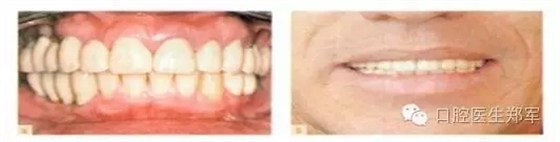

•最終評估暫時修復(fù)體的美學(xué)和功能,將暫時修復(fù)體轉(zhuǎn)移到最終修復(fù)體上(圖11);

•通過交叉上牙合架技術(shù)復(fù)制暫時修復(fù)體到最終修復(fù)體上(圖12)。

圖12 a和b最終修復(fù)體(圖由修復(fù)學(xué)專家Dr 0 Gelfan, Professor Z Artzi , and Mr B lndig.提供) |